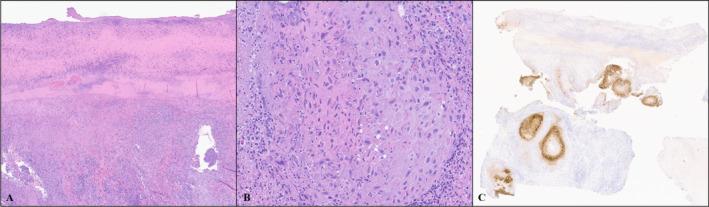

Mpox (formerly known as monkeypox), a zoonotic disease caused by Monkeypox virus (MPXV), has become an international outbreak since May 2022. Mpox often presents with a mild systemic illness and a characteristic vesiculopustular skin eruption. In addition to molecular testing, histopathology of cutaneous lesions usually shows distinctive findings, such as epidermal necrosis, balloon degeneration, papillary dermal edema, and focal dermal necrosis, which have proven helpful in the diagnosis of mpox. Viral cytopathic changes with areas of multinucleation, smudging of the nuclei, and intracytoplasmic inclusions have also been described. Although useful, these features are relatively nonspecific. The use of a monoclonal antibody for immunohistochemical (IHC) staining of MPXV may be a useful tool in confirming mpox infection.

METHODS

Three cases of PCR-confirmed mpox were biopsied and subjected to IHC staining with a monoclonal MPXV-specific antibody targeting viral envelope protein A29. As controls, cell lines transduced to express other MPXV viral antigens and samples of cutaneous viral infections involving Molluscum contagiosum, Herpes simplex, Herpes zoster, or Cytomegalovirus were also subjected to IHC staining with this antibody.

RESULTS

All three mpox patient biopsies performed on lesional skin subjected to MPXV IHC staining reliably detected viral infection in lesional skin with a diffuse cytoplasmic and focally nuclear staining pattern. No staining was seen in transduced cell lines expressing off-target MPXV viral antigens and in lesional skin of other common viral infections listed above.

CONCLUSIONS

The monoclonal MPXV-specific antibody may be used as an adjunct tool to confirm mpox infection.